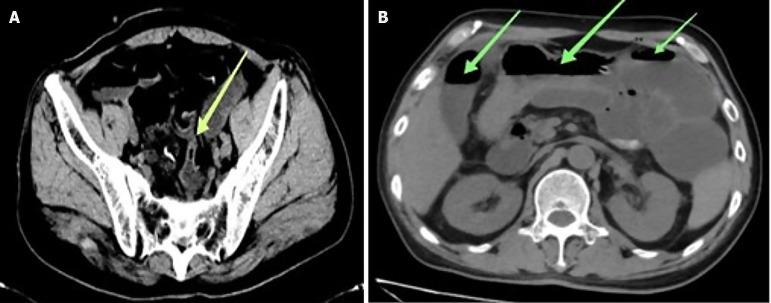

A patient experienced recurrent difficulty in bowel movements over the past decade. Recently, symptoms worsened within the last ten days, leading to a clinic visit due to constipation. The patient was subsequently referred to our department. Preoperatively, the patient was diagnosed with obstructed colon accompanied by gallstones. Empirical antibiotics were administered both before and after surgery to prevent infection. On the fourth day post-surgery, symptoms of CDI emerged. Stool cultures confirmed the presence of DNA. Treatment involved a combination of vancomycin and linezolid, resulting in the patient's successful recovery upon discharge. However, the patient failed to adhere to the prescribed medication after discharge and was discovered deceased during a follow-up two months later.

一名患者在过去十年中反复出现排便困难。最近,症状在过去十天内加重,因便秘前来就诊。该患者随后被转诊至我科。术前,患者被诊断为结肠梗阻伴胆结石。手术前后均给予经验性抗生素以预防感染。术后第四天,出现了CDI症状。粪便培养证实存在艰难梭菌DNA。治疗采用万古霉素和利奈唑胺联合使用,患者出院时成功康复。然而,患者出院后未遵医嘱服药,两个月后随访时被发现死亡。